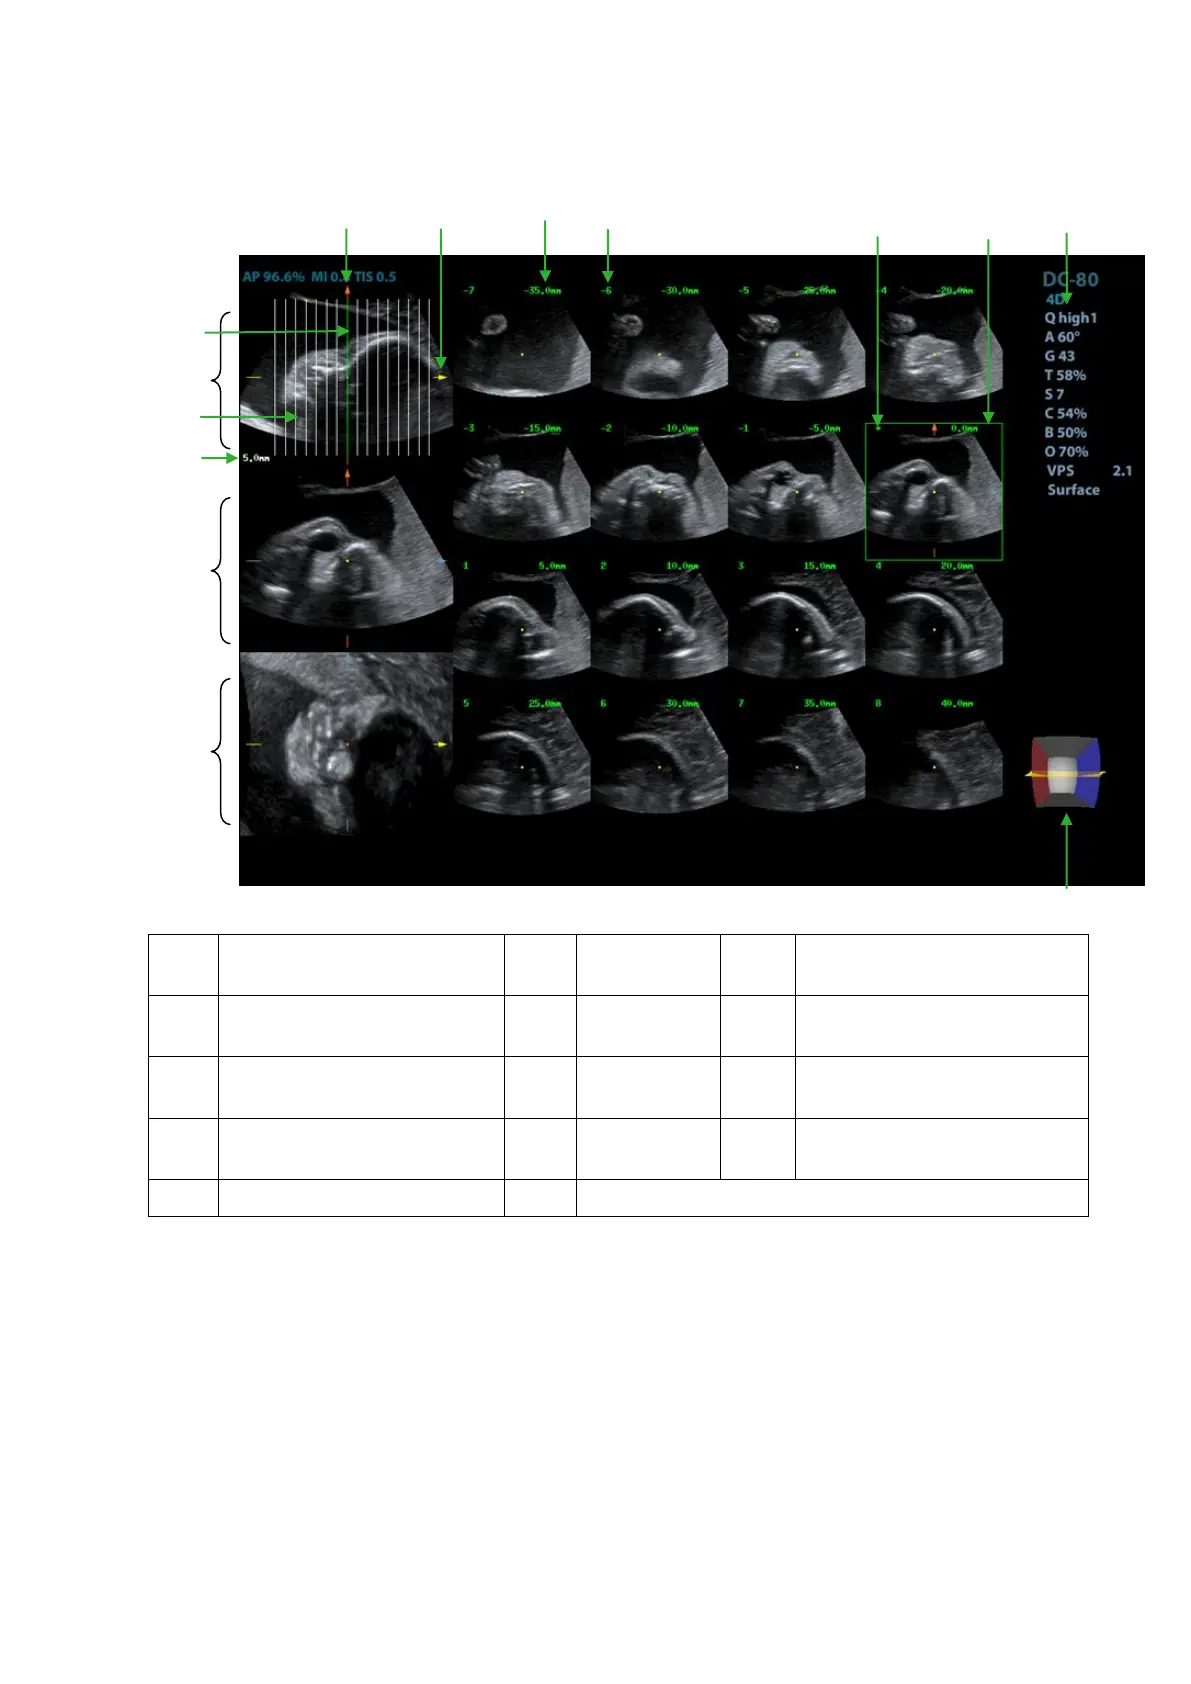

5.10.8.2 Basic Screen & Operation

<1>

A plane (the current

reference image)

<2>

B plane

<3>

C plane

<4>

Central slice line(Current

active slice)

<5>

Slice line

<6>

Space between two slice

lines

<7>

Y-axis

<8>

X-axis

<9>

Slice position (to the central

slice)

<10>

Slice order number

<11>

Central slice

mark

<12>

Active slice be highlighted in

green

<13>

Image parameter

<14>

Wire cage

The system supports several types of displaying layout: 2*2, 3*3, 4*4 and 5*5, touch the

corresponding icon on the touch screen to select, and the selection [Slice Number] changes

accordingly.

Reference image

Touch [A], [B], or [C] to select the reference image.

Slice and slice line

Central slice: the central slice line corresponding plane are the central slice, which is

marked with a green ―*‖ at the upper left corner of the image.